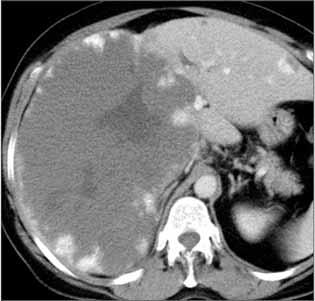

Rycina 38.40. Rycina 38.41.

Ogniskowy rozrost guzkowy (FNH – focal nodular hyperplasia)